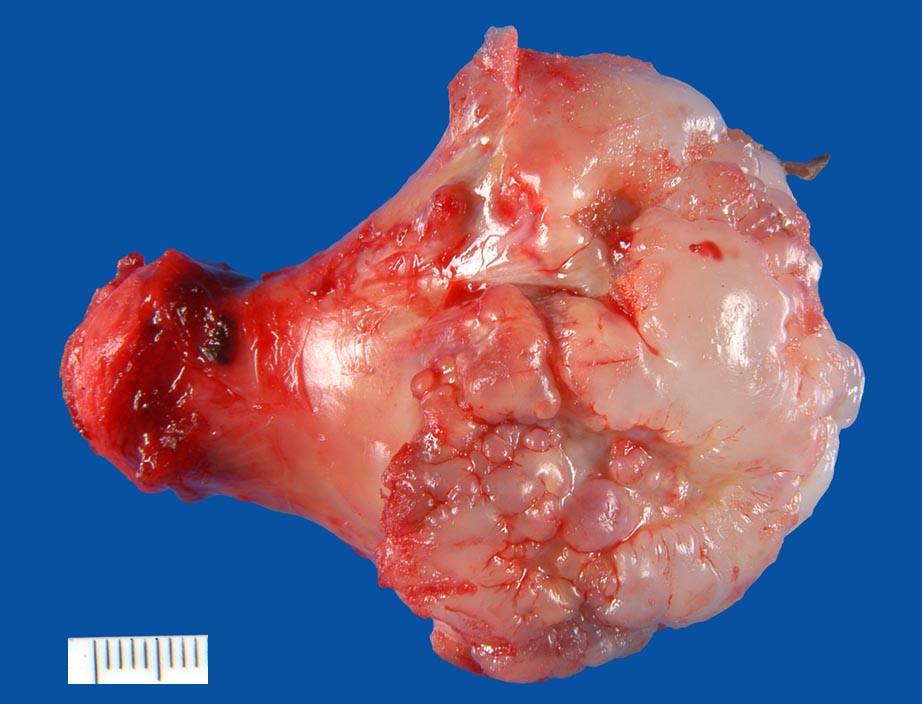

Osteochondrome sind breitbasig dem Knochen aufsitzende oder gestielte knöcherne Tumoren, die von einer 1-6mm dicken Kappe aus hyalinem Knorpel bedeckt werden. Zwischen Knorpel und Knochen liegt eine Zone enchondraler Ossifikation, die der normalen Wachstumsfuge ähnelt und den Ausgangspunkt für die Grössenzunahme des Tumors bei noch nicht abgeschlossenem Skelettwachstum darstellt. Der hyaline Knorpel wirkt etwas unorganisiert und ist bedeckt von einer dünnen Schicht Perichondrium.

• Kappenförmiges hyalines Knorpelgewebe ohne Zellatypien sitzt auf einem knöchernen Stiel. Die Knorpelkappe ist 2mm dick.

• Knorpelkappe bedeckt von einem schmalen Saum zellarmen Bindegewebes (=Perichondrium).

• Übergang des Knorpels in enchondrale Ossifikationszone wie in einer Epiphysenfuge: Knochen wird abgelagert entlang von linearen Knorpelsäulen.